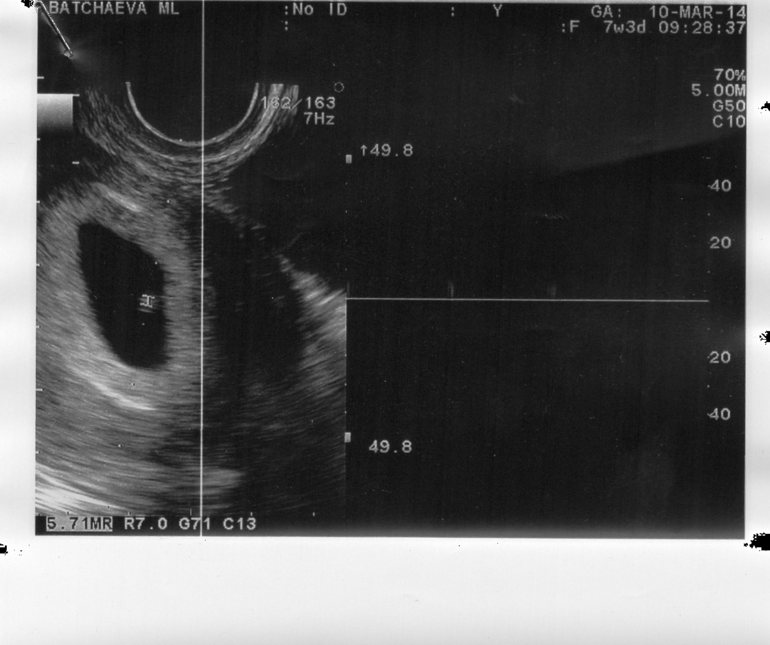

ага с лева) и небольшая точка отмеченная узисткой) справа регистрация сердцебиения. сдесь нам 5 и 4 (аппарат очень хороший и узистка, нас искали так как акушерский больше был и ставили зб)